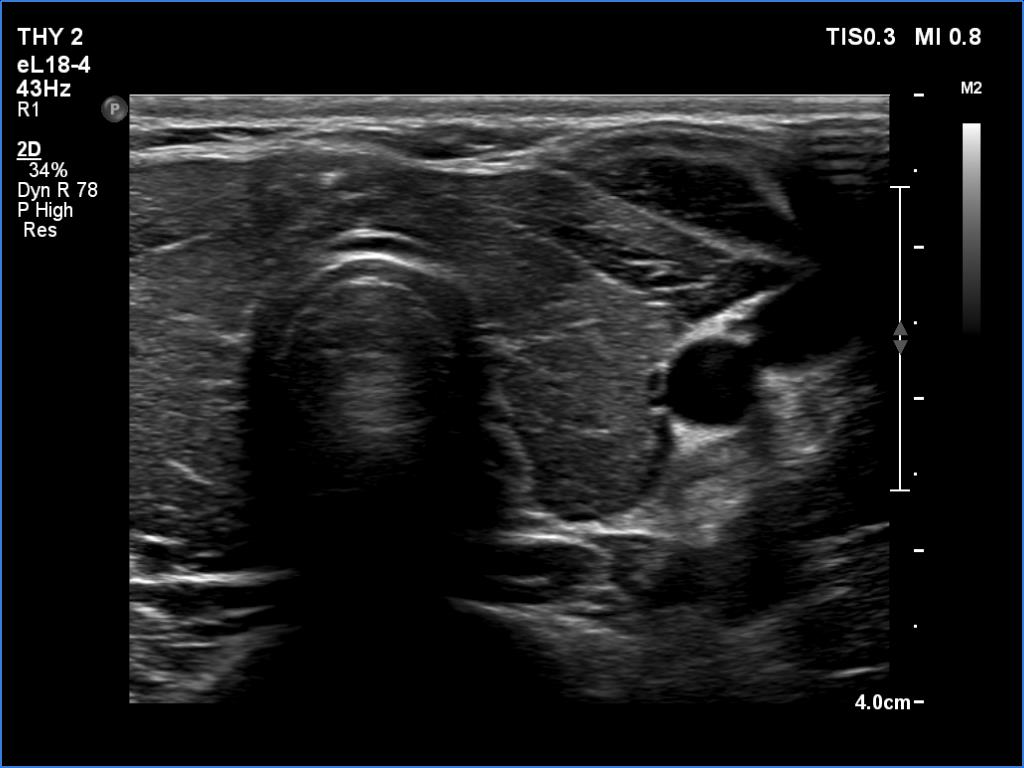

Ultrasonography. The thyroid was moderately hypoechoic and inhomogeneous. There was a deeply hypoechoic lesion in the isthmus which presented microcalcifications. Compared with the extranodular tissue, the nodule was much less vascularized on Doppler and microflow imaging but was harder on elastography.

Compared with nodules found in either lobe, the ultrasound signs of extrathyroidal spread are even more controversial in a nodule which is located in the isthmus. Such nodules necessarily present abutting and bulging contours.

There were two conditions which favored that the discrete lesion in the isthmus is a true nodule and not a more active focus of the underlying Hashimoto's thyroiditis. Firstly, the palpation which itself was suspicious of a cancer. Second, the presence of microcalcifications. It is worth comparing the similarly deep hypoechoic areas in the left lobe with the presentation of the cancer focus.